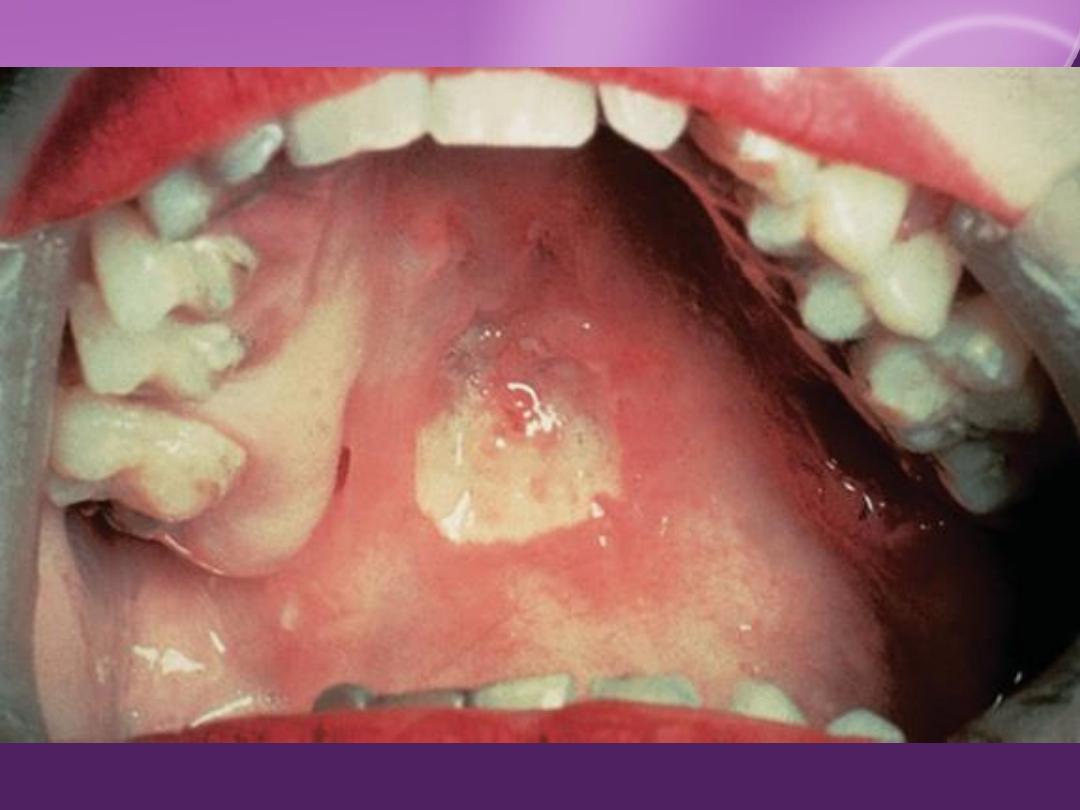

MM involvement

Condylomata lata

Oral lesions

MM Lesions:

palate, nasal mucosa, tongue, tonsils, and pharynx

Oral leukoplakia

50%